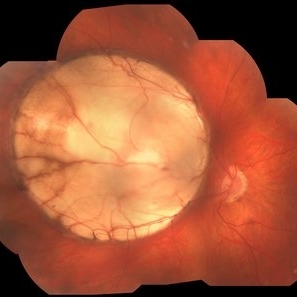

Retinal detachment, Coloboma

Male patient, 58 years old, PIO 19-21, AV; OD 20/200, OS 20/20. He had sudden low vision, with progressive worsening in his right eye. He underwent evaluation in retinal mapping and further examinations where important funduscopic changes were found. Both eyes had an atrophic lesion suggestive of coloboma of the retina in the lower arch. Right eye with retinal detachment with macular involvement.

Photographer: JEFFERSON ROCHA DE SOUSA - Retinal Department at Instituto Dr. Suel Abujamra Sao Paulo-Brazil

Imaging device: Clarus 700 - Zeiss, composite of four 135 degree images.

Condition/keywords: coloboma, coloboma of choroid, Retinal Detachment